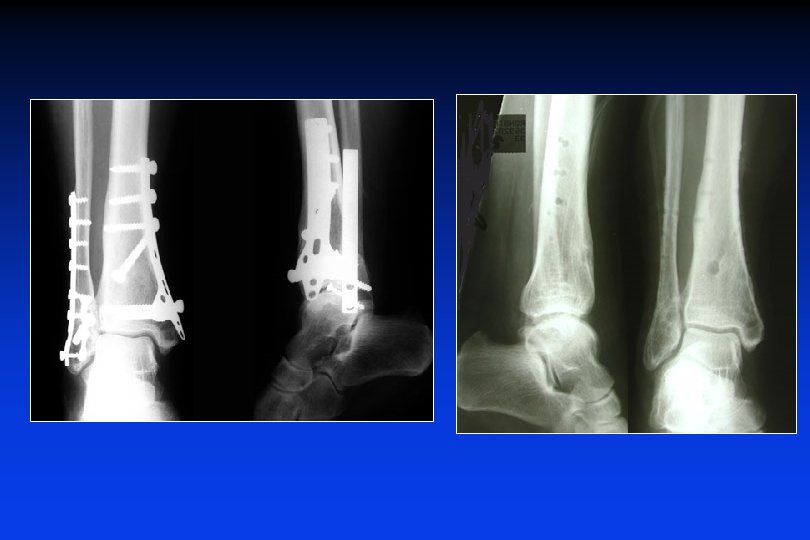

• • Sintesi anatomica del perone (ristabilire la lunghezza) ricostruire la superfice articolare (fili + viti) Fissatore esterno sulla tibia o tra la tibia e l’astragalo

• • Sintesi anatomica del perone (ristabilire la lunghezza) ricostruire la superfice articolare (fili + viti) Fissatore esterno sulla tibia o tra la tibia ed il calcagno